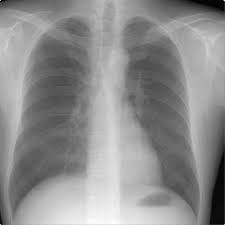

A student-chef with a history of asthma suffered a sudden onset of back and chest pain. A chest x-ray and CT angiogram were diagnosed as pneumonia, and not an embolism. Four months later, he collapsed at home. Tests revealed a massive pulmonary embolism, which affected his brain. An expert testified that, had the tests been properly reviewed and blood thinners issued four months earlier, the embolism would not have developed. The man is permanently blind and his left arm is paralyzed.